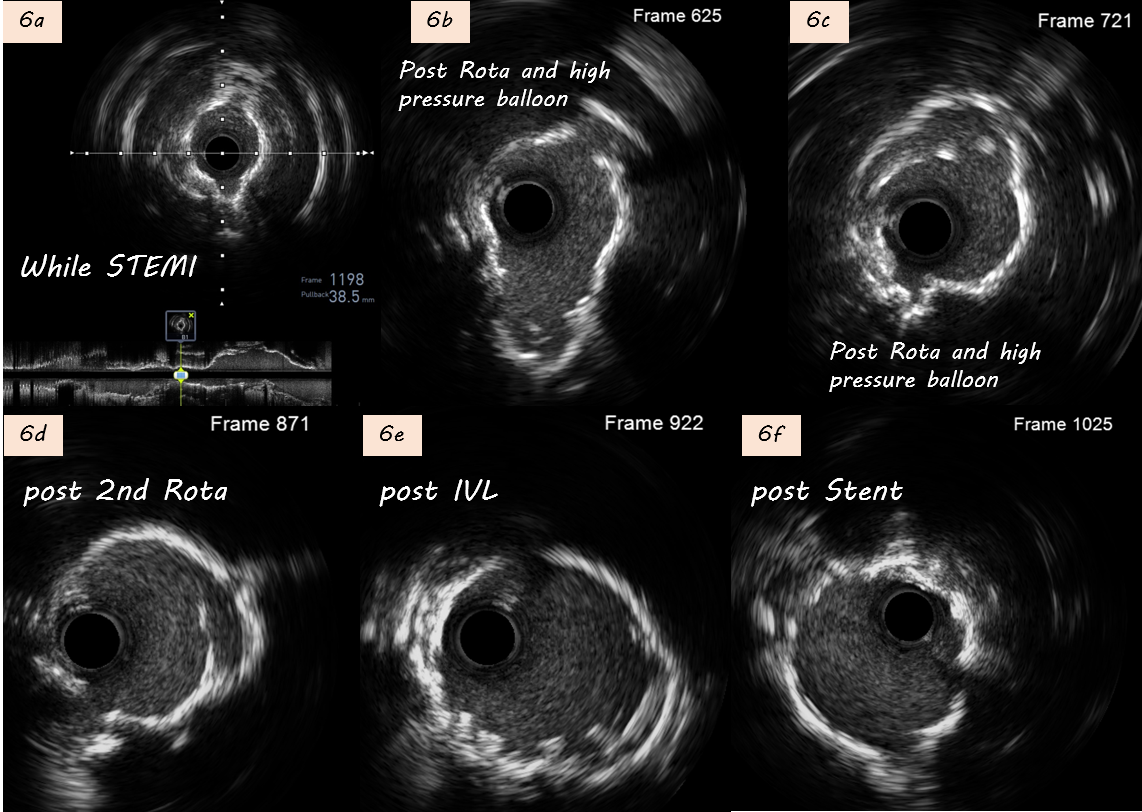

During 1st PCI, IVUS showed severe calcification in LAD seg6 (Fig. 2a). Rotablation with a 2.0 mm burr was performed (Fig. 2b), and a 3.5¡¿28mm Multi-Link BMS was implanted but remained underexpanded (Fig. 2c).STEMI developed one week later prompted repeat CAG showing subacute thrombosis within LAD stent (Fig. 3a). Thrombus aspiration was performed. POBA with a 3.5¡¿15mm Raiden balloon (up to 24 atm) failed to fully expand the stent (Fig 3b). Subsequently, a 3.5¡¿30mm MagicTouch DCB was used.During 3rd PCI,rotational atherectomy was performed with 1.75mm and then 2.0mm burrs; however, 2.0 mm burr entrapment occurred during lesion crossing, and angiography showed limited debulking effect (Fig 4a-b). High-pressure balloon with APT NC 3.5x12mm were attempted but rupture(30 atm). We then POBA with Raiden 3.5¡¿15mm (30 atm), Raiden 4.0¡¿15 mm (32 atm), and NC Euphora 4.5¡¿15mm (20 atm). Finally, 4.0x40mm B. Braun DCB angioplasty was performed (Fig 4c).4th PCI was performed 1 month later for intravascular lithotripsy (IVL) and new stent implantation. Second time rotablation with a 1.75 mm burr was performed (Fig. 5a-b). IVL with a 4.0¡¿12mm balloon (100 pulses) achieved adequate expansion (Fig. 5c–d). Adequate POBA were followed by final stenting using a 4.0¡¿23mm Firehawk DES (Fig. 5e). Proximal optimization technique and kissing balloon technique were performed (Fig. 5f). Serial IVUS showed better debulking after 2nd Rotablation and IVL, and adequate new stent expansion (Fig 6a-6f).

Case Summary